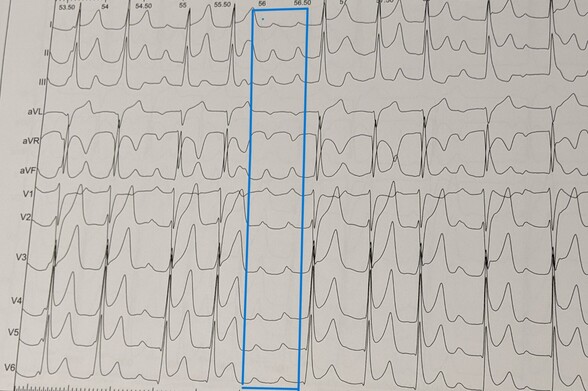

43-year-old female with frequent palpitations, multiple times per week, particularly after exercise. What are our thoughts on rhythm and origin?

#epeeps #ECG #Ekg #cardioed #Cardiology #electrophysiology #CardioTwitter